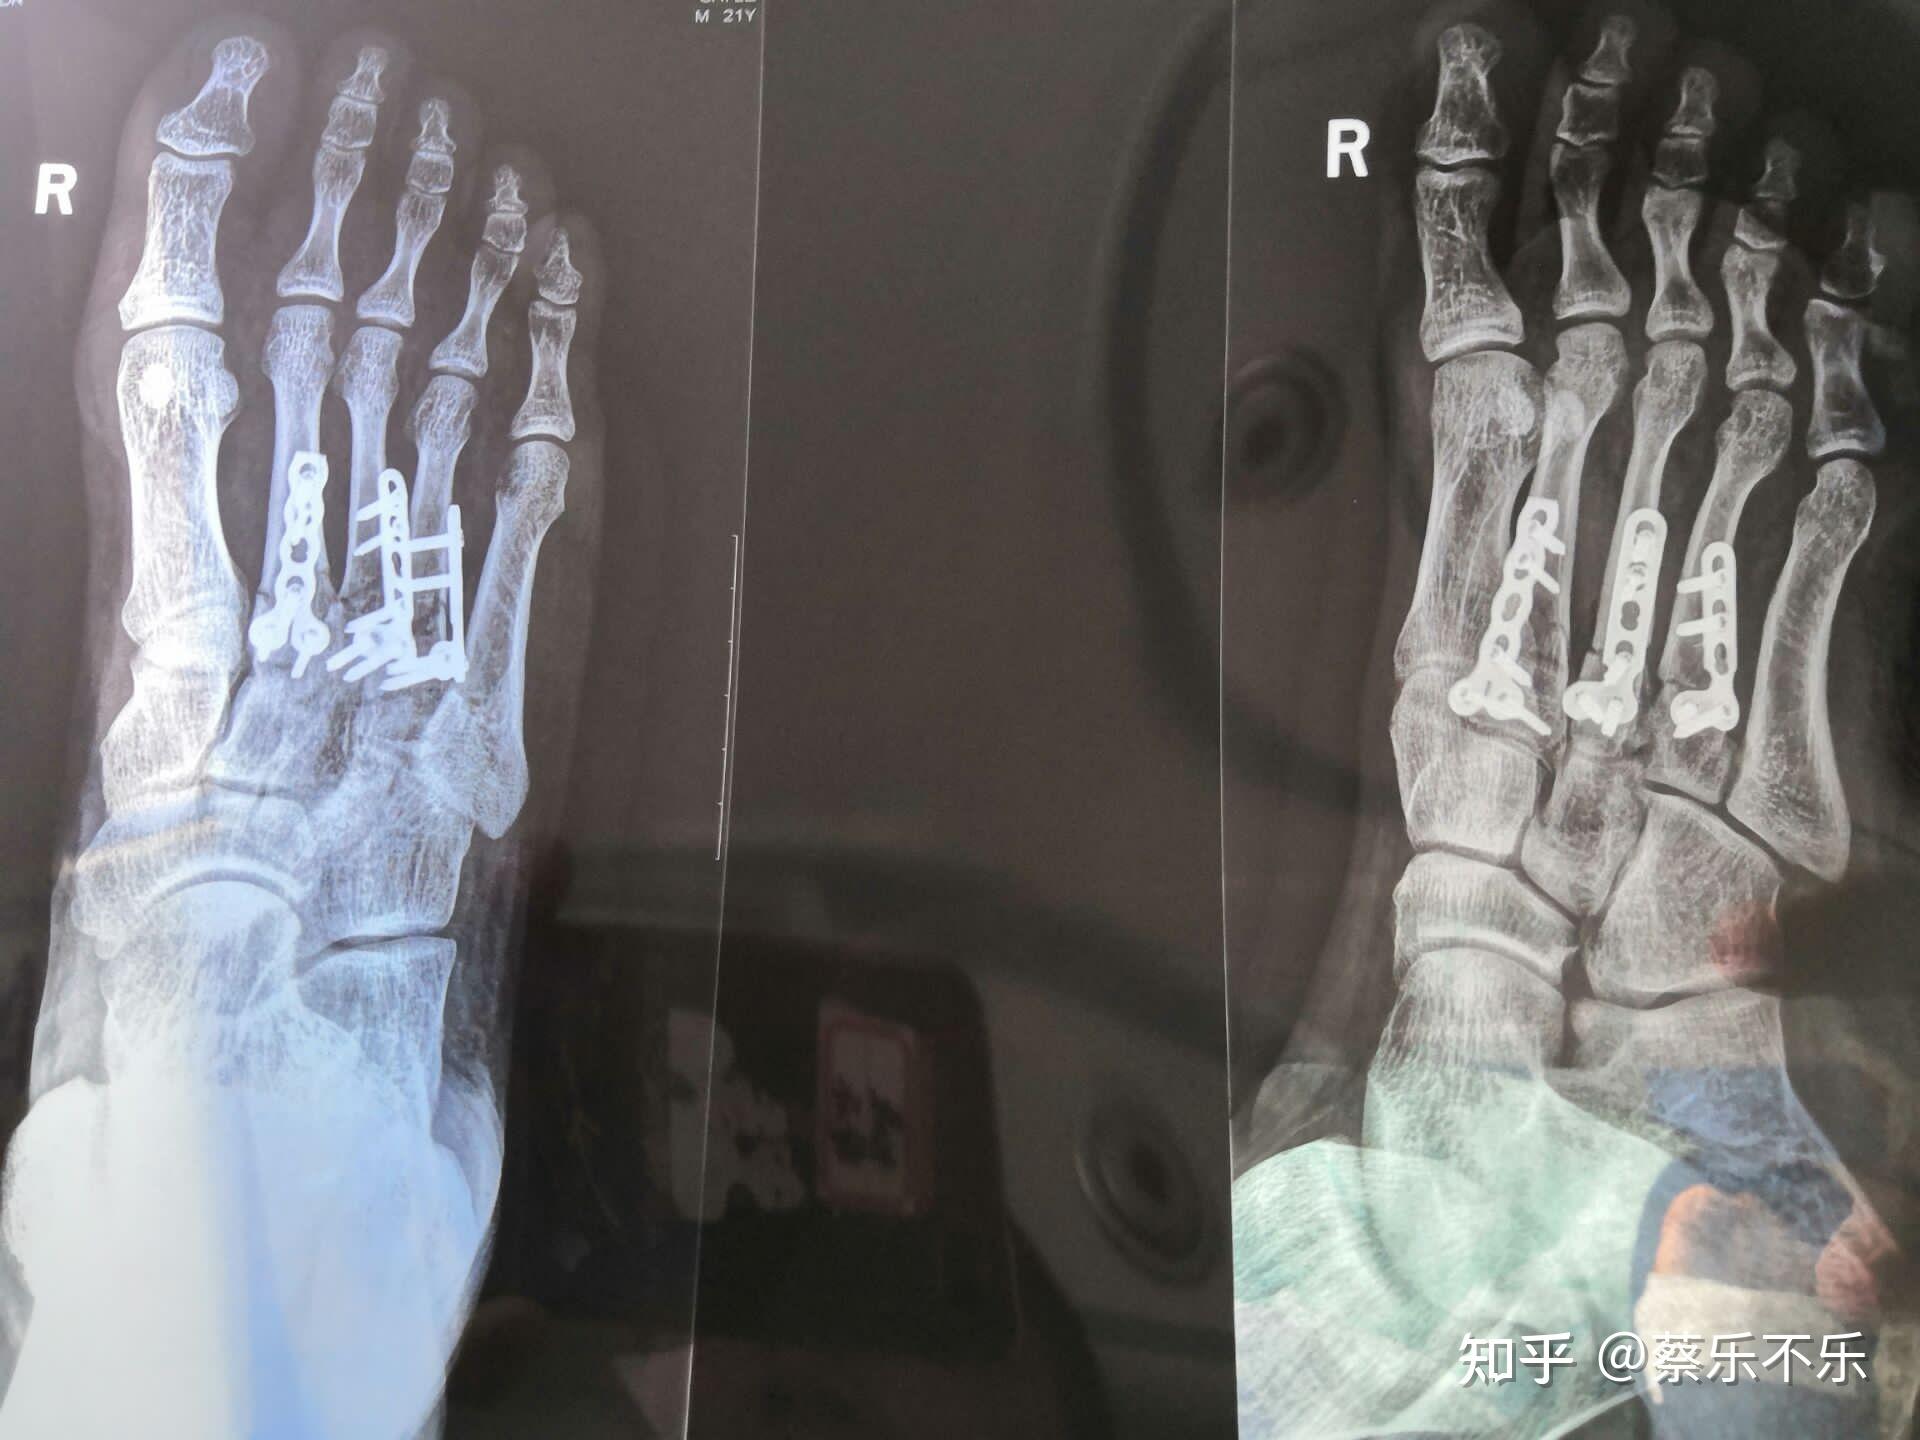

8日,做的右足跖骨第二三四切开内固定手术(就是打钢板)坐标武汉,四五

图片尺寸1920x1440